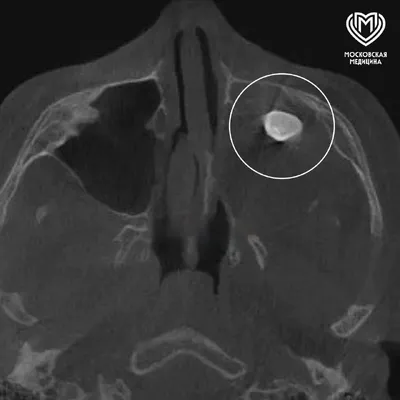

У подростка в носу вырос зуб . 15-летний парень жаловался на заложенность носа и асимметрию лица. Обследование показало, что в гайморовой пазухе сформировался зуб. После его удаления заложенность п